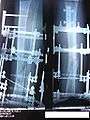

X-Ray of the fracture site, part 1 (two months following fracture)

X-Ray of the fracture site, part 2 (two months following fracture)

X-Ray of the fracture site (three months following fracture). Note formation of bone callus around fracture site.

X-Ray of the fracture site, part 2 (three months following fracture). Note formation of bone callus around fracture site.

X-Ray of the fracture site, part 2 (four months following fracture)